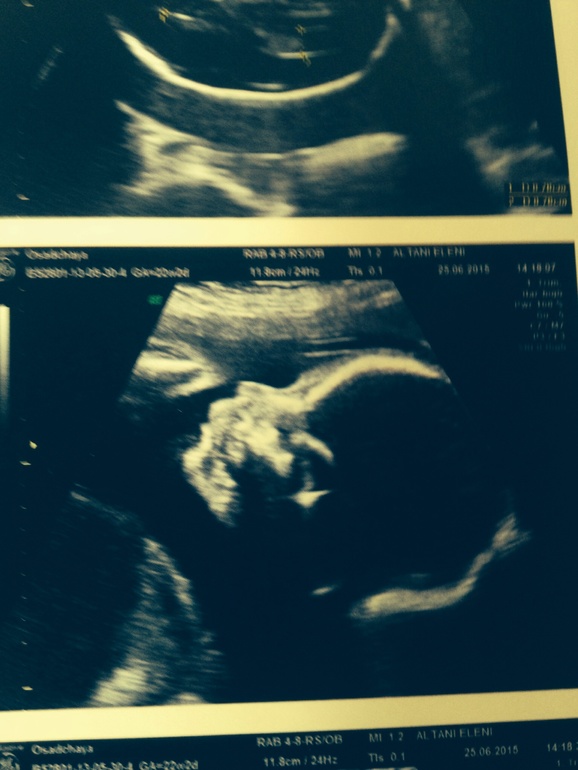

Дочь

на втором снимке нос острее, подбородок также более острый, губы разные и даже форма головы - ну это на мой взгляд.